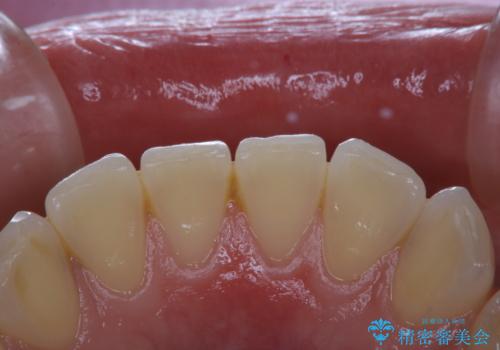

PMTC60分コース(保険外治療)を行いました。かなり久しぶりの歯科医院へ来院とのことで、プラーク(歯垢)・歯石・ステイン(着色)が付着していました。汚れを除去し、本来のご自身の歯質にすることでなにか異常があった際に発見しやすくなります。

PMTCで汚れを除去することは、虫歯や歯周病・口臭予防に効果的です。